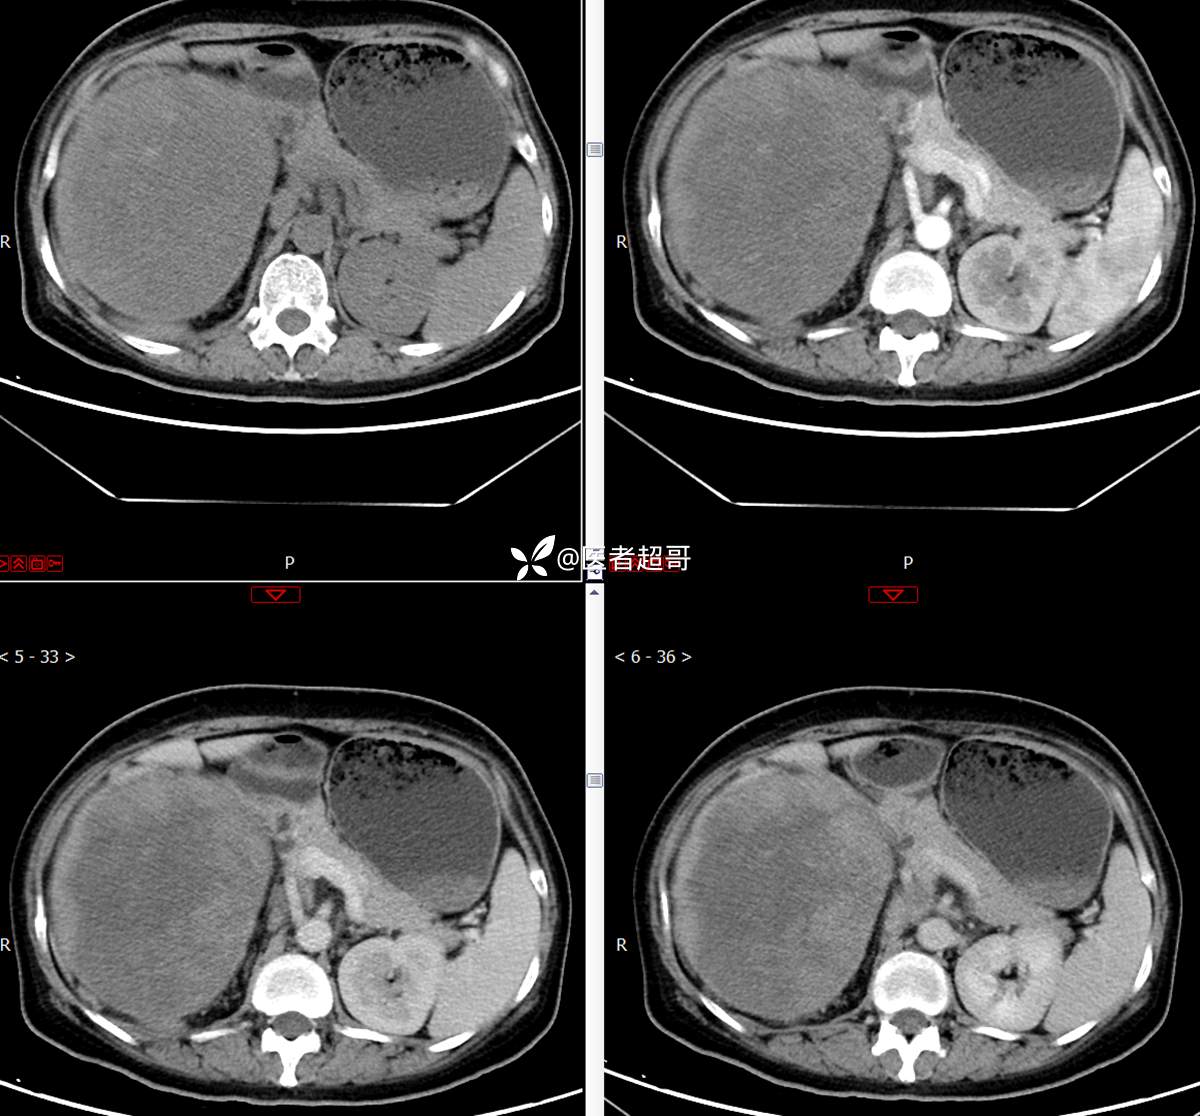

【影诊笔记743】腹腔肿物?腹膜后肿物?请先定位,后定性!有病理!

主 诉:发现右上腹肿物1周余。

现病史:患者1周余前发现右上腹有一半球形巨大肿物,约18cm*15cm大小,既往贫血病史3年余,诉乏力,易疲劳,偶有头晕,活动后心悸,无腹痛、腹胀,无恶心、呕吐,无尿频、尿急、尿痛,无排尿困难,患者为求进一步治疗,来我院消化内科就诊,门诊行肝.胆.胰.脾.肾彩超示:右肾上部囊实性占位,范围约18.0cm×11.7cm×16.4cm,边界清,形态规则,建议进一步检查,腹膜后实性结节。我科遂以“肾肿物”收治入院,患者自发病以来,神志清、精神可,睡眠、饮食可,二便正常,体重、体力略有下降。